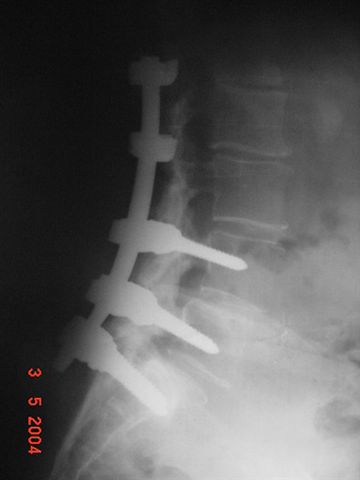

Paciente del sexo femenino de 79 años de edad.

Por problemas en la columna laminectomía y fijación.